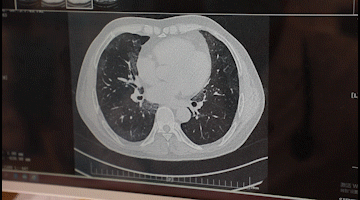

李先生入院后,胸科醫(yī)院吳昌歸院長、朱運(yùn)奎副院長組織科室進(jìn)行了深入討論,為其做了詳細(xì)檢查。醫(yī)生先做了導(dǎo)航下氣管鏡冰凍活檢,但病理未獲明確診斷。根據(jù)胸部CT特征、病變過程治療的反應(yīng),醫(yī)生懷疑是罕見的肺泡蛋白沉積癥。再經(jīng)肺泡灌洗液分析、PAS染色及診斷性分段灌洗后復(fù)查,證明醫(yī)生診斷正確。李先生確診為“肺泡蛋白沉積癥(繼發(fā)性)、肺炎、1型呼吸衰竭,并伴有慢性乙肝、高血脂癥等。

經(jīng)過4次的治療,李先生沉著于肺泡內(nèi)蛋白樣物質(zhì)漸漸消失,灌洗液為透明色。復(fù)查胸部CT肺部病變明顯吸收。經(jīng)再次灌洗治療后病變完全吸收,恢復(fù)健康。